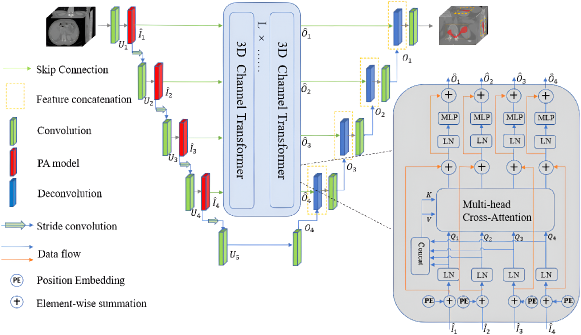

In computer vision, transformers can be divided into pure and hybrid ones. In pure transformers, the MSA modules are used in both the encoder and decoder. Hybrid transformer architectures fuse the ViTs with convolution modules in the encoder, bottleneck, decoder, or skip connections to combine information about the global context and local details (Azad et al., 2024). Swin-UNet is a pure transformer with a UNet-like architecture (Fig. 6) employing the Swin transformer block in the encoder, bottleneck, and decoder (Cao et al., 2023a). CTUNet is a hybrid network (Fig. 7) for segmentation of the pancreas parenchyma with 3D channel transformer blocks inserted into the skip connection of a 3D UNet (Chen and Wan, 2022). A pancreas attention module with a project and excite block was designed and added to each encoder to enhance the ability to extract context information, while cross attention was inserted between the output of each transformer and decoder to eliminate semantic inconsistency (Chen and Wan, 2022).